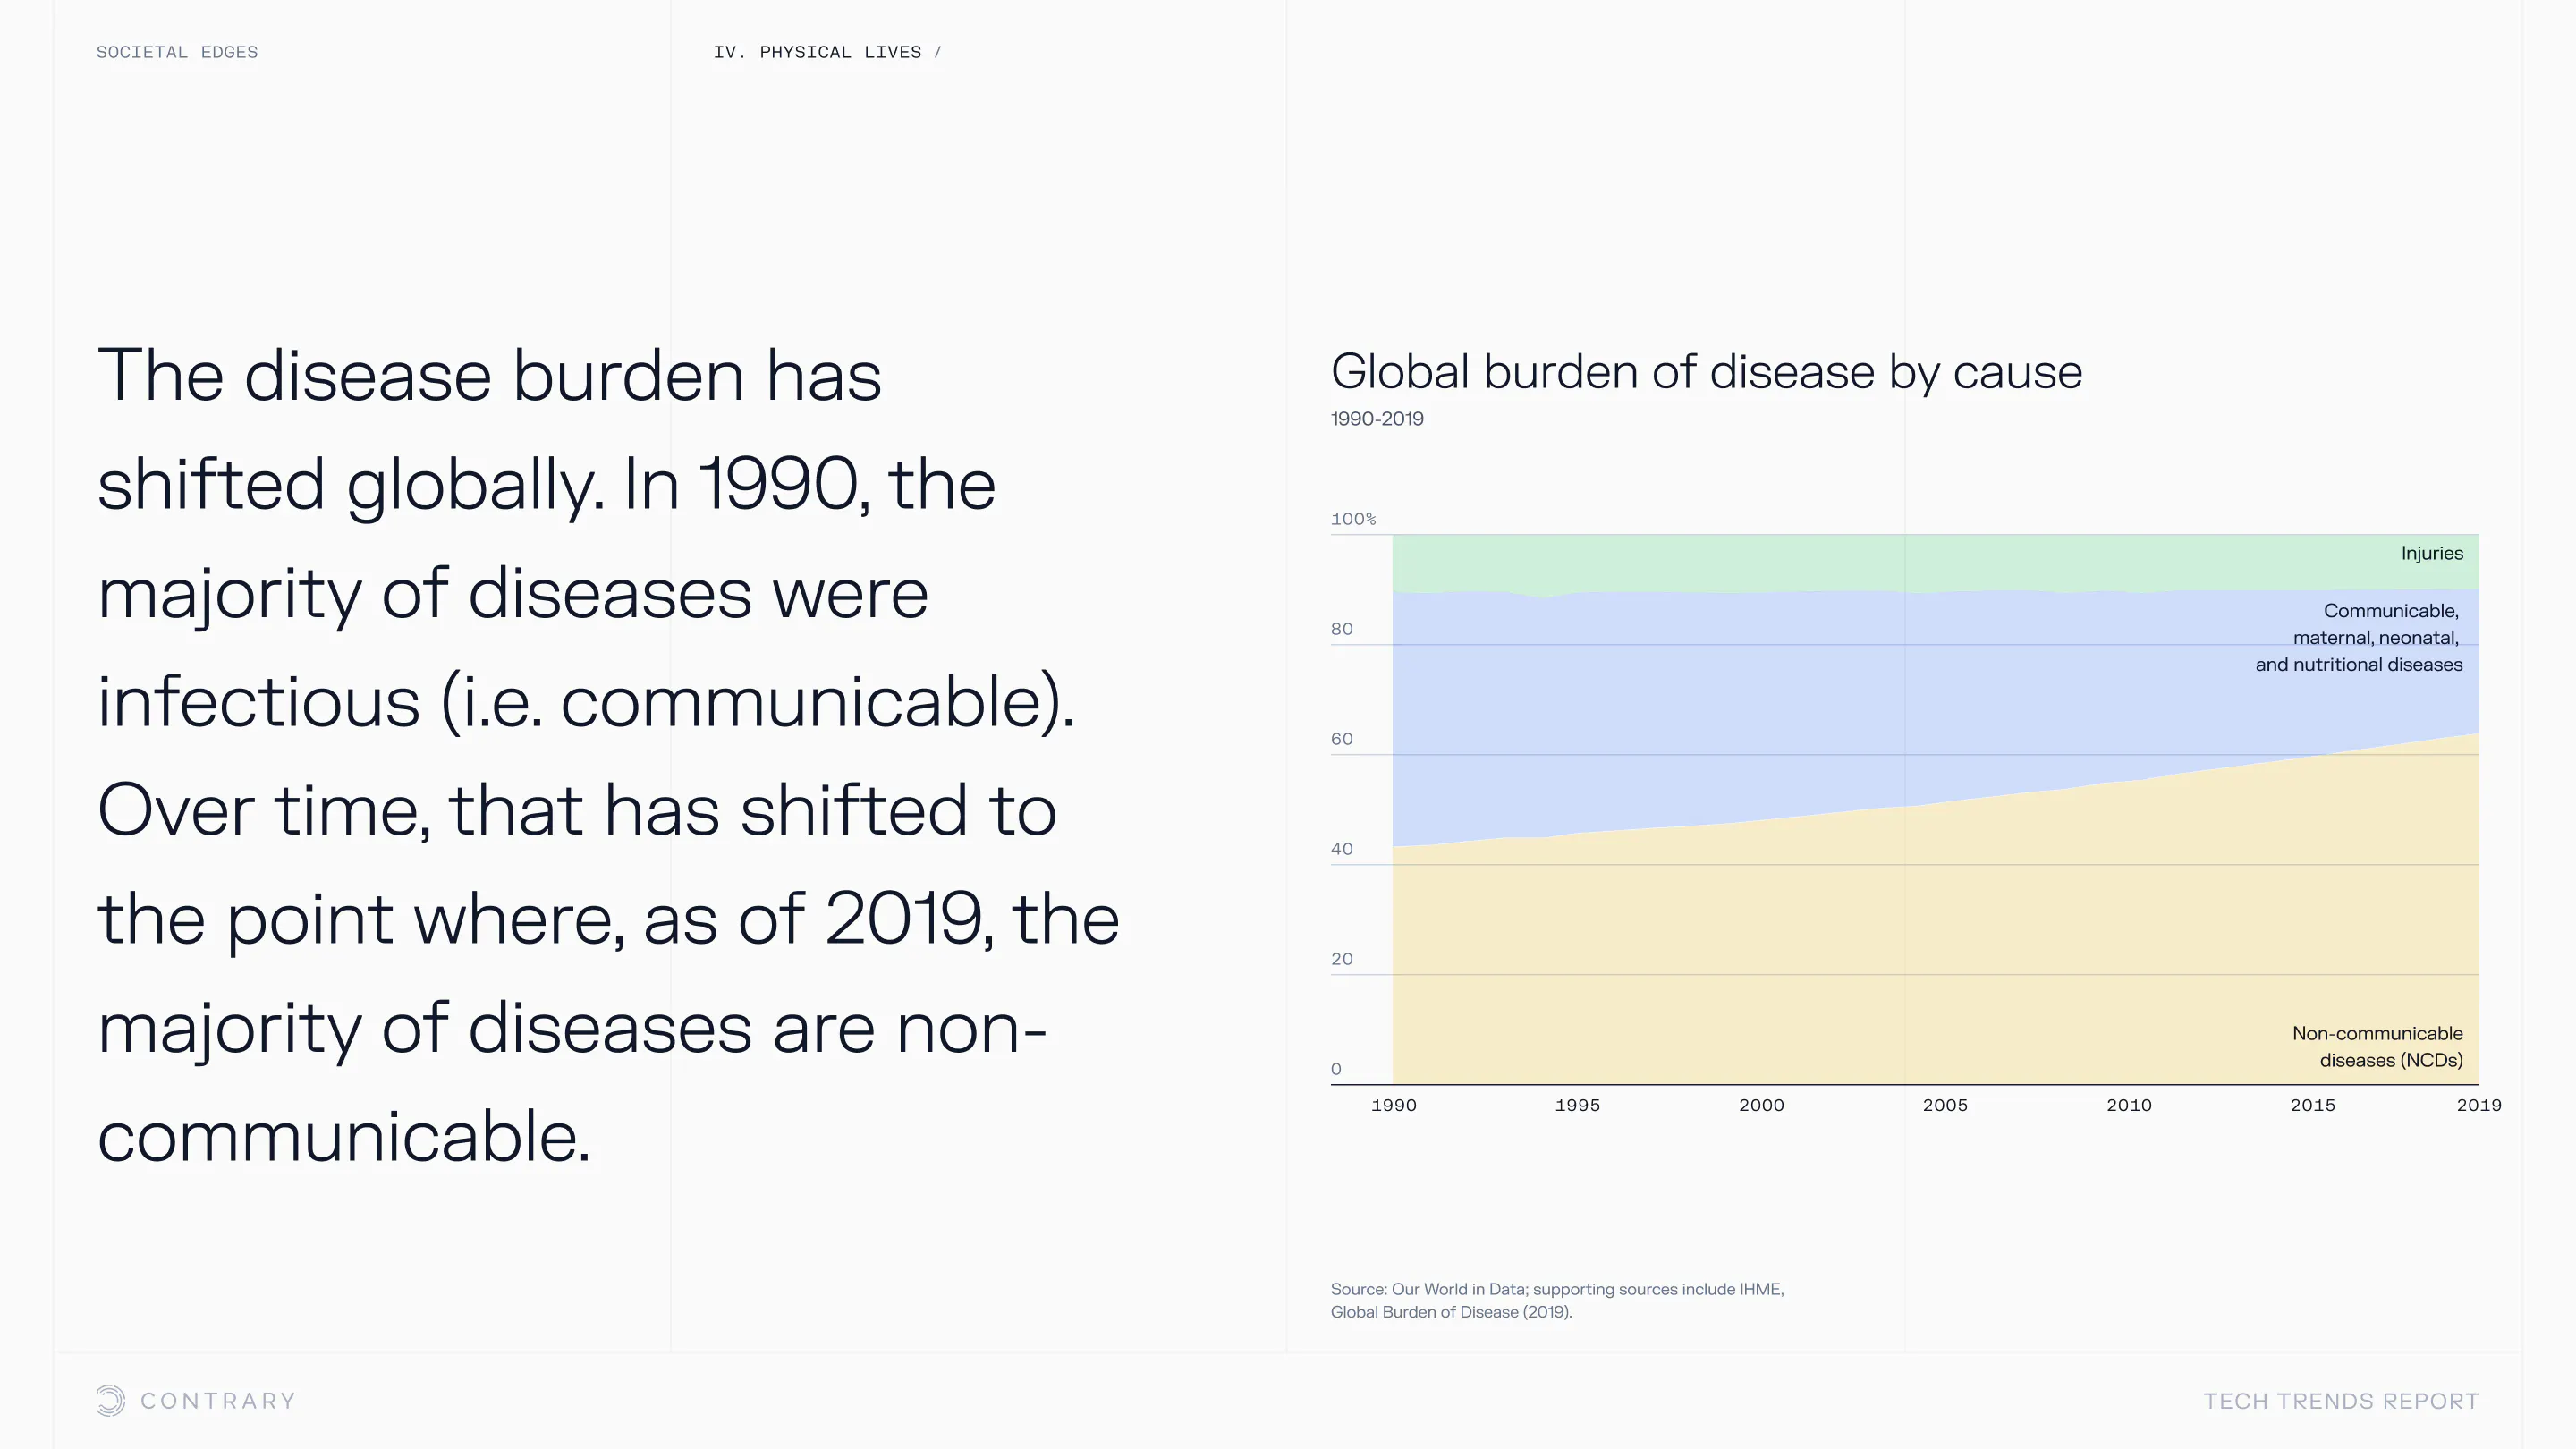

An aging population is bringing up a range of increased concerns, from mental health to disease control. Obesity and gastrointestinal cancers are plaguing younger generations. The cutting edge is tackling a system that has unhealthiness woven into it.